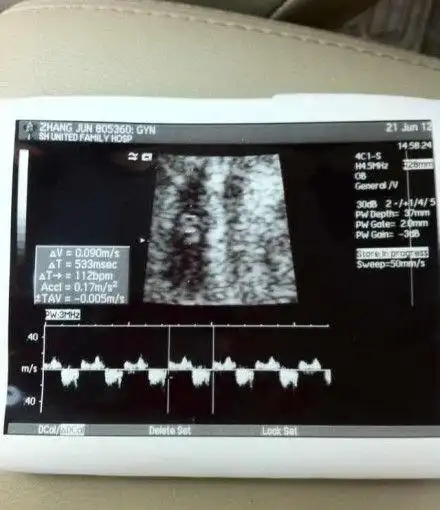

到尾时间也未足一月,今日,陈龙章龄之微博晒出两人爱情结晶婴儿b超照

在b超单上,我们一般会发现这3个名词,双顶径就是头部最宽部位的长度